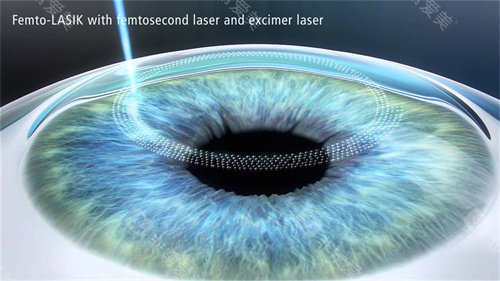

免核黄素浸泡步骤,手术时长缩短至10分钟

采用370nm比较准紫外线,对角膜内皮零损伤

飞秒激光辅助移植吻合精度达0.01毫米

2016年优先引入经美国FDA认证的角膜交联系统,2025年升级至第五代设备,紫外线能量控制精度高。

无锡分院2025年引入全光塑近视激光手术,结合交联术为角膜条件欠佳者提供解决方案。